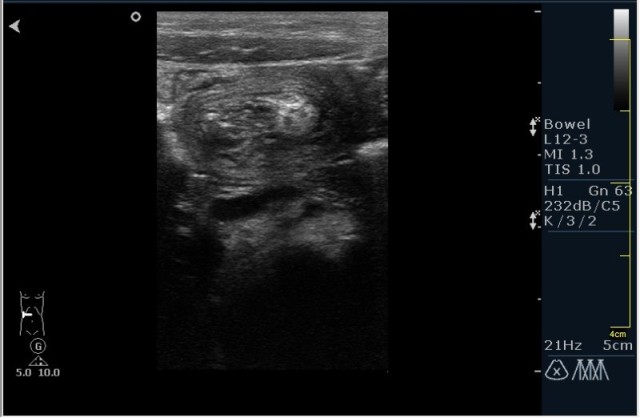

Ребёнок с болями в животе.

инвагинация! :!:

На представленных сонограммах определяется типичная "мишень" или "кокарда" (7ая и 8ая сонограмма сверху), которая при продольном сканировании превращается в "телескоп" (сонограммы 3 & 4). Все это указывет на инвагинацию кишечника (илео-цекальную). Причиной явилось лимфаденопатия брыжейки (которую вы указали). Увеличеные лимфоузлы вместе с инвагинатом хорошо различимы в просвете толстой кишки.

Уважаемые коллеги! Без сомнения имеет место илео-цекальная инвагинация.увеличенные овальные лимфоузлы, да еще такими гроздями характерны для мезаденита.Все зависит от развертывания клинической симптоматики.